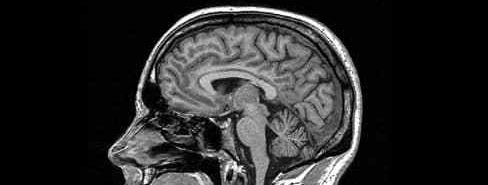

During my fledgling medical career, I’ve come across a variety of diseases and drug names that make no damn sense. Half the battle in learning pharmacology is being able to repeat drug names that sound more like the title of a D-movie playing at 3 a.m. on the sci-fi channel than comprehensible english (Seriously, you try to pronounce Levetiracetam or Eculizumab).

However, no drug or disease or anatomical structure with a ridiculous name has truly bothered me like pseudopseudohypoparathyroidism. When I first laid eyes on this asinine collection of letters on page 331 of my 2017 edition of First Aid, I was immediately taken aback. I read it to myself several times over, trying to see if my mind or eyes were playing tricks on me. To my dismay and disappointment, there truly exists a disease named pseudopseudohypoparathyroidism.